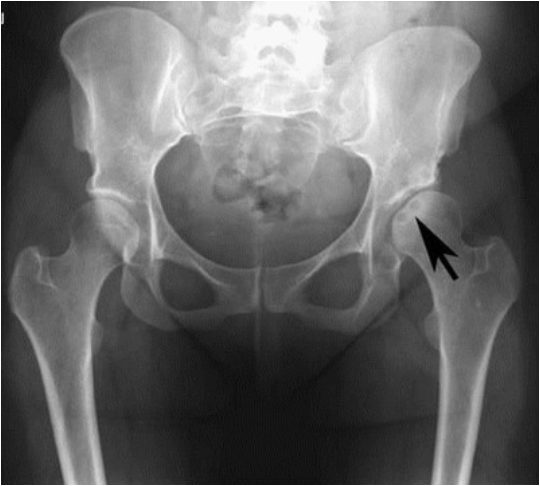

В ортопедии и травматологии рентгенологическое исследование используют для диагностики деформирующего коксартроза, артритов, асептического некроза головки бедренной кости, костных новообразований, вывихов, переломов шейки бедра и т. д. Рентгтенография позволяет подтвердить наличие патологии, но не всегда дает достаточно информации. Нельзя, например, получить послойное изображение тканей, из-за чего врачи не могут определить точную локализацию патологических изменений.

Симптомы и синдромы, которые выявляют с помощью рентгенографии:

- сужение суставной щели. Признак дистрофических изменений суставных хрящей. Этот симптом выявляют у больных с деформирующим остеоартрозом и хроническими артритами;

- остеопороз. Снижение плотности костей. Характеризуется уменьшением количества костных балок в единице объема костной ткани. Патология развивается в пожилом возрасте. Сам остеопороз протекает бессимптомно, но на его фоне зачастую развивается деформирующий остеоартроз и переломы шейки бедра;

- деструкция. Возникает вследствие инфекционного процесса. Характеризуется разрушением участков кости с их дальнейшим замещением гноем, грануляциями или опухолевой тканью. Наличие деструкции может указывать на парапротезную инфекцию, остеомиелит, злокачественные новообразования;

- некроз. Неинфекционное омертвение костной ткани. Чаще всего участки некроза появляются в области головки бедренной кости. Причина – возрастное ухудшение кровотока и обмена веществ.

Выявление того или иного признака на рентгенограмме косвенно указывает на определенную патологию. Часто для постановки диагноза врачу хватает данных анамнеза, осмотра и рентгенографического исследования.